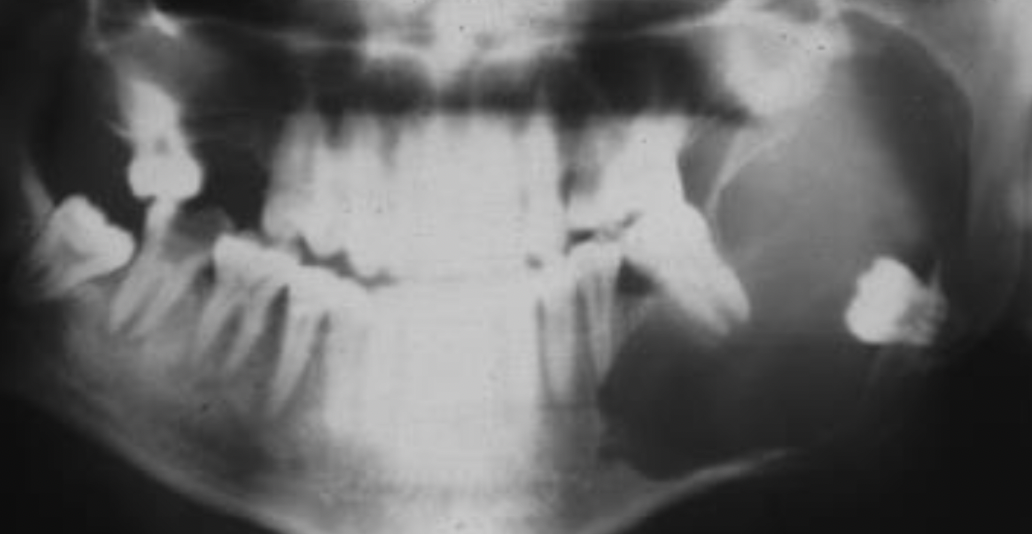

A

dentigerous cyst

Q

expansion of dentigerous cyst